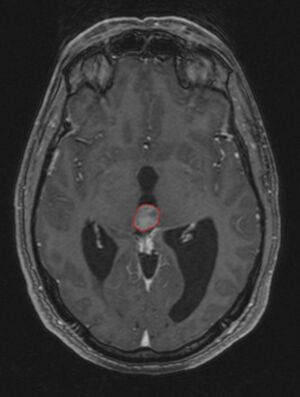

ورم الغدة الصنوبرية هو ورم من الغدة الصنوبرية ، وهي جزء من الدماغ التي تنتج الميلاتونين. إذا دمر الورم الصنوبري خلايا الغدة الصنوبرية عند الطفل ، فيمكن أن يسبب البلوغ المبكر.

في كثير من الأحيان ، يُعرف شلل الحملقة إالعلوي جنبًا إلى جنب مع العديد من الموجودات العينية مثل رأرأة تراجع التقارب وتراجع الجفن المعروف أيضًا باسم علامة كولير وانفصال الضوء القريب (تتكيف الحدقة مع الضوء ولكنها لا تتفاعل مع الضوء) يسموا كمجموعة بمتلازمة بارينو[1] أو متلازمة الدماغ المتوسط الظهرية ، هي الأعراض الجسدية الوحيدة التي تظهر. يحدث هذا بسبب ضغط مركز الحملقة العمودي في سقف الدماغ المتوسط على مستوى الأكيمة العلوية والعصب القحفي III. يتضمن العمل عادةً التصوير العصبي كما يظهر على اليمين.[بحاجة لمصدر]